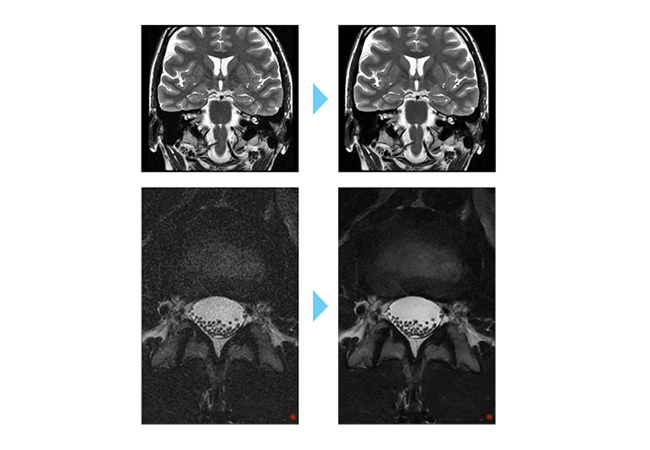

Deep Learning AIR™ IQ Edition(MR30)

AIを使った画像再構成にて高磁場装置のような高画質画像

1.5T MRIに最新技術を導入したことで、撮像時間のかかる分解能の高い検査内容でもAIR™ Recon DL( AI:深層学習)により画質が向上しました。AIR™ Recon DLは、空間データ全体に直接ディープラーニング画像再構成を応用し、「ノイズ低減」、「画像 尖鋭度の向上」、「トランケーションアーチファクト低減」の3つの効果が同時に得られる画期的な技術です。

画像のクオリティ向上による診断精度向上

MRIは検査時間が長いため、動きがあった場合は、撮りなおしを行っていた検査でした。新技術により、仰向けになられず、動きによりアーチファクトがあっても、診断の効率向上や患者様の負担軽減に貢献します。